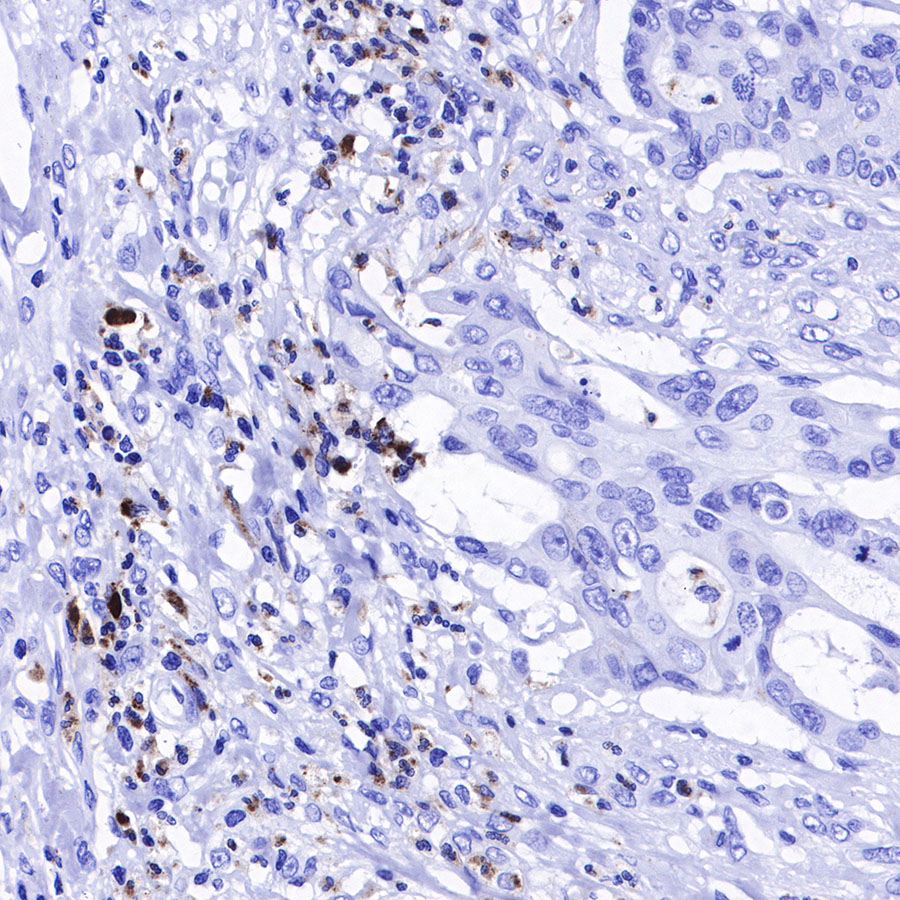

Immunohistochemistry

IHC shows positive staining in paraffin-embedded human liver. Anti-Lysozyme antibody was used at 1/100 dilution, followed by a HRP Polymer for Mouse & Rabbit IgG (ready to use). Counterstained with hematoxylin. Heat mediated antigen retrieval with Tris/EDTA buffer pH9.0 was performed before commencing with IHC staining protocol.